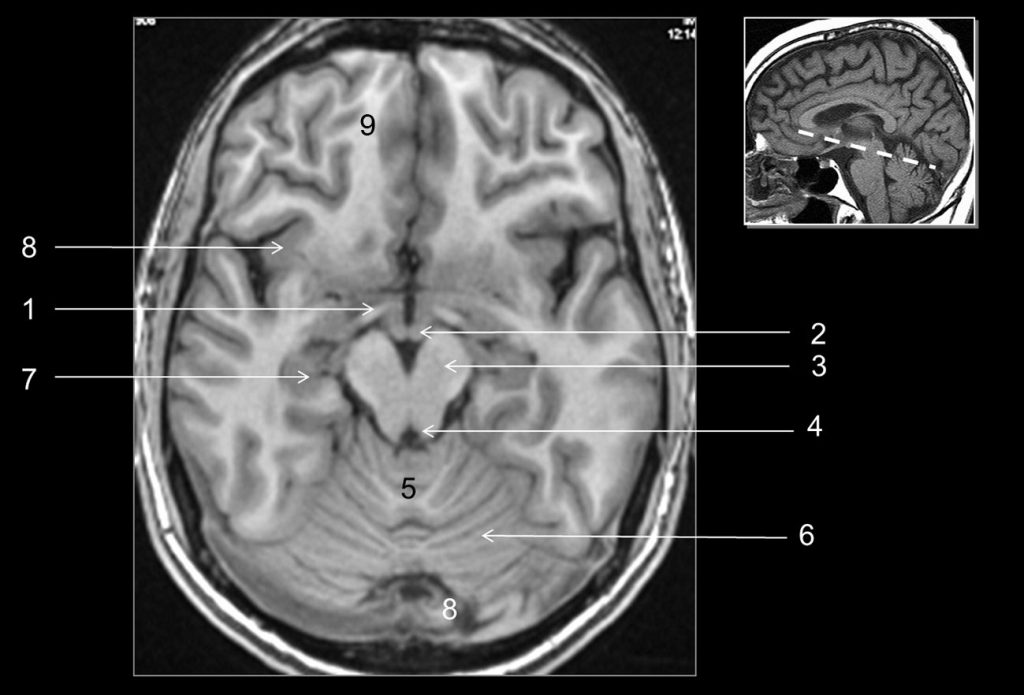

Fig. 48.5 Coupe axiale (IRM) en pondération T1.

1. Tractus optique. 2. Corps mamillaire. 3. Pédoncule cérébral. 4. Aqueduc du mésencéphale. 5. Vermis. 6. Hémisphère cérébelleux. 7. Hippocampe du lobe temporal. 8. Cortex insulaire. 9. Lobe frontal.